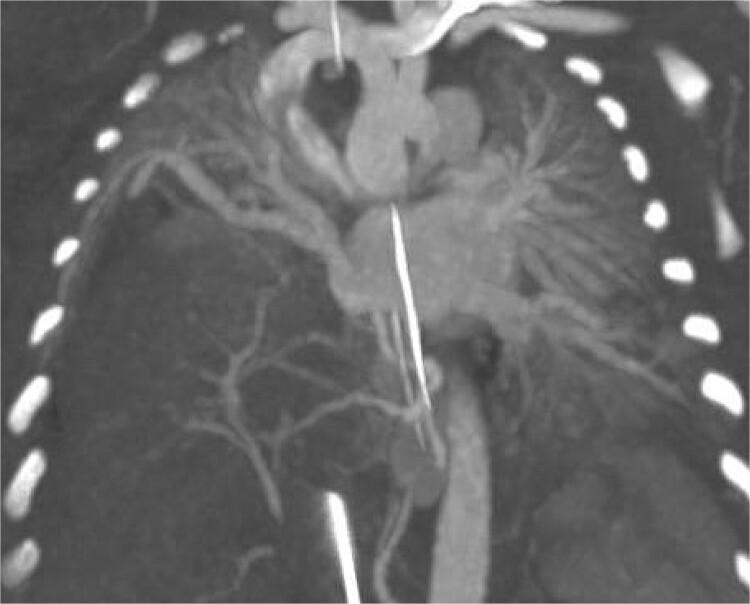

Right sided congenital diaphragmatic hernia (CDH) associated with hepatopulmonary fusion (HPF) is a rare congenital anomaly in which the herniated liver is fused with lung parenchyma. We discuss the case of an infant with right-sided CDH and HPF found on index operation for repair of right-sided CDH. Due to the high incidence of vascular anomalies associated with HPF the decision was made to close the patient and get further imaging to characterize the HPF before returning to the operating room for definitive repair. We describe a novel and successful operative approach where the liver was left entirely fused to the lung and the liver was partially brought down from the chest and was plicated to the diaphragm form a seal between the parietal and pleural cavities to repair the CDH.

右侧先天性膈疝(CDH)合并肝肺融合(HPF)是一种罕见的先天性异常,其中疝入的肝脏与肺实质融合。我们讨论了一例在初次手术修复右侧CDH时发现右侧CDH合并HPF的婴儿病例。由于与HPF相关的血管异常发生率较高,决定关闭患者并进行进一步成像以明确HPF的特征,然后再返回手术室进行确定性修复。我们描述了一种新颖且成功的手术方法,即让肝脏完全与肺融合,将肝脏部分从胸腔下拉并折叠到膈肌上,在壁层和胸膜腔之间形成密封以修复CDH。